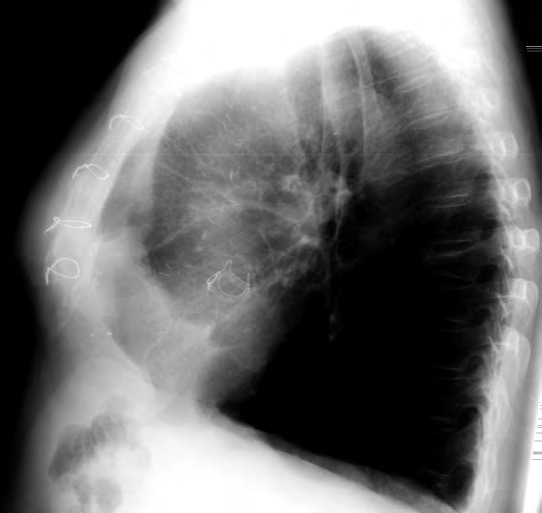

Zeichen eines Pneumomediatinums

• Zervikales Weichteilemphysem • Parakardiale / paraaortale Hypertransparenz mit lateraler Begrenzung durch die Pleura parietalis • Sub- / retrokardiale Luft mit kontinuierlicher Darstellung des Zwerchfells • Thymus-Segel-Zeichen beim Kind („spinnaker sign“) • Pneumothorax • Pneumoperikard • Luft um Pulmonalarterienring (Seitaufnahme)